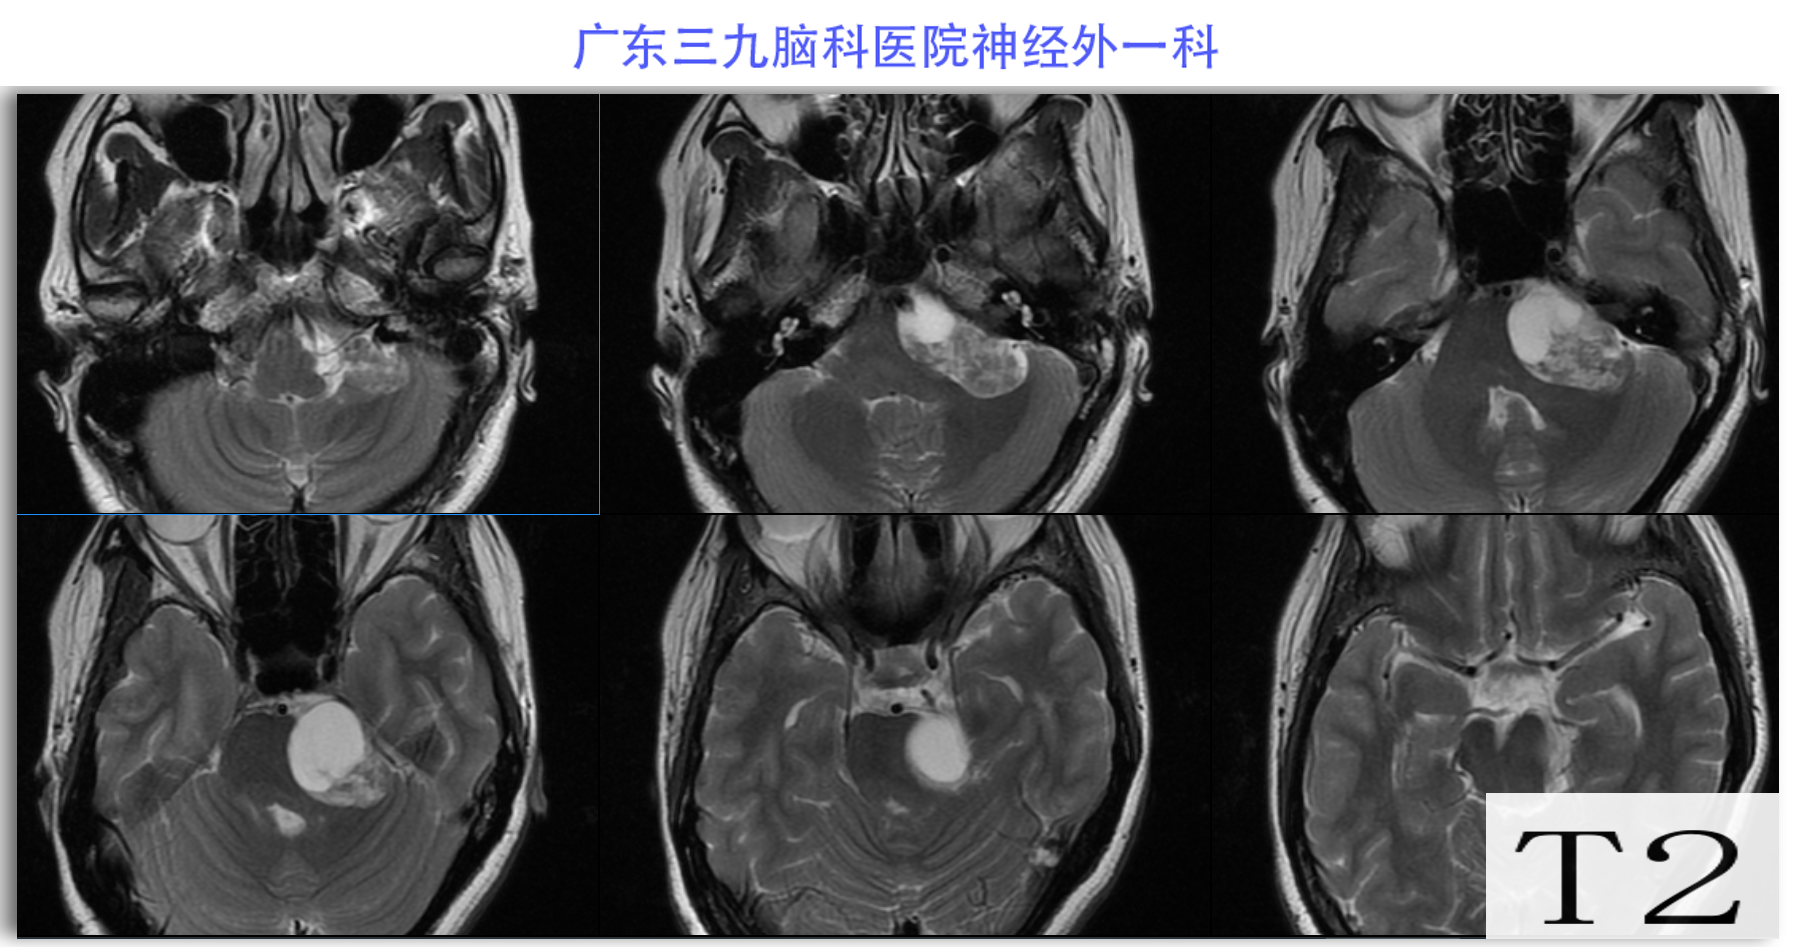

陈某某,女,41岁,因“左侧面部麻木3月余,吞咽困难半月余”于2024-02-17入院。患者3个月前出现左侧面部麻木,偶尔伴有头晕和左侧流泪,但没有听力下降或耳鸣。同时,患者也出现肢体乏力和行走不稳,但未接受任何治疗。半个月前,患者发现吞咽硬质食物稍有困难,同时左侧面部麻木加重。因此,前往当地医院就诊,并进行头颅MR检查,结果显示左侧CPA区存在占位性病变。为了进一步治疗,患者转诊至我院就医。术前检查显示:左侧角膜反射减弱,左侧鼻唇沟略微变浅,伸舌稍微右偏,咽反射迟钝。门诊诊断为“左侧巨大听神经瘤”,收治至我科进行住院治疗。手术过程顺利,术后患者恢复良好,面部轻度瘫痪与术前相同。术后病理检查结果确认为听神经瘤。